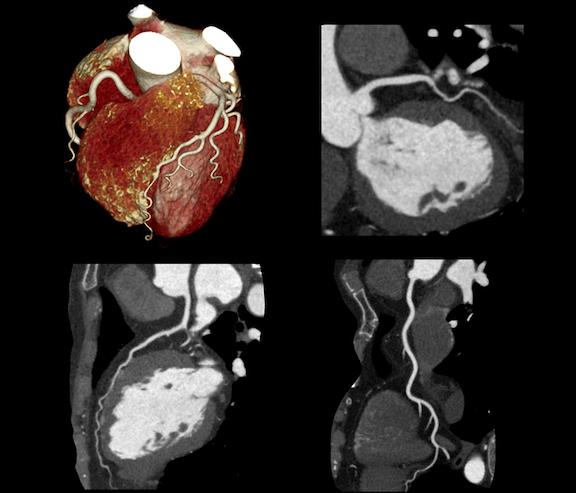

January 27, 2021 — Philips Healthcare has introduced the Philips Abdominal Aortic Aneurysm (AAA) Model, providing ...